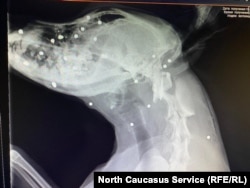

Пострадала Лелька, годовалая сучка. Марина бросила все и повезла ее в ветклинику. Из собаки достали 20 металлических осколков. Московские волонтеры предложили помощь, и собаку отправили рейсом в столицу. Сейчас ее состояние – стабильное, средней тяжести, по словам врачей, угрозы жизни нет. Тем не менее, существует вероятность, что собака лишится зрения.